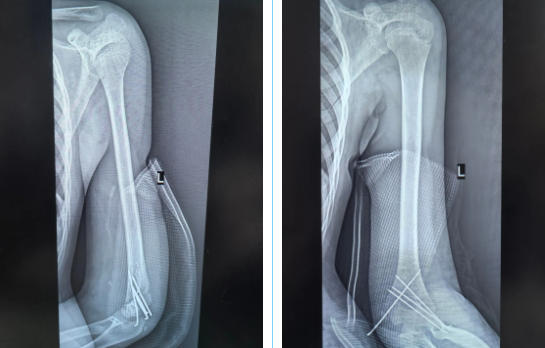

术后影像

手术于当日进行,吕红兵副主任医师主刀,小心翼翼地修复受损神经,开展左肱骨骨折复位内固定术,手术顺利结束,患者安返病房。之后几天里,患者桡动脉搏动恢复正常,左手麻木逐渐消失,于7月25日顺利出院。